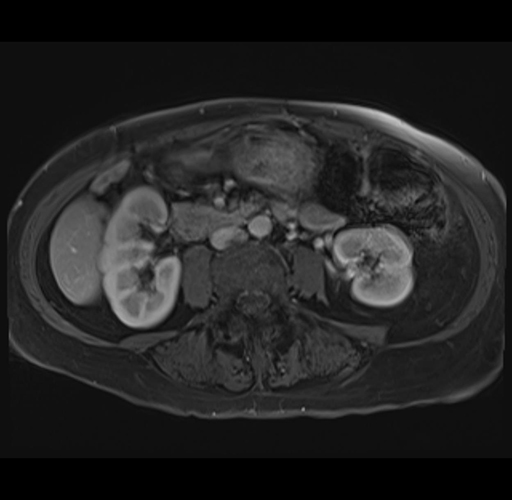

MRI T1